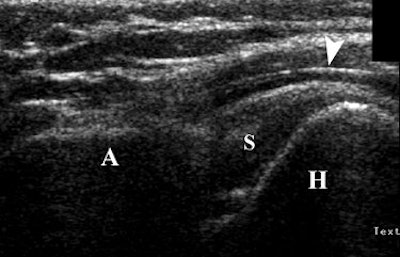

During this active exam, the relationship between the acromion, humeral head, and soft tissues were assessed. If the humeral head passed easily underneath the acromion during shoulder movement, then impingement was ruled out, the authors stated. Otherwise, readers looked for soft-tissue or osseous impingement.

| Forty-three-year-old man with upward migration of humeral head during dynamic sonography evaluation of shoulder. Coronal sonography view of left shoulder with shoulder impingement syndrome, during active elevation of arm halfway between flexion and abduction with hand in pronation, shows abnormal upward migration of humeral head (H) in regard to acromion (A), preventing its passage underneath acromion. There is mild distension of subacromial bursa (arrowhead). S = supraspinatus tendon. Bureau NJ, Beauchamp M, Cardinal E, Brassard P, "Dynamic Sonography Evaluation of Shoulder Impingement Syndrome" (AJR 2006; 187:216-220). |

According to the results, there were 14 shoulders with subacromial impingement. In this group, 14% were diagnosed on dynamic sonography and 50% of those were given a grade 3. In the 12 asymptomatic shoulders, 75% were given a grade 0.

"In grade 3 subacromial impingement, there is a failure of the humeral depression resulting in upward migration of the humeral head," Bureau's group stated, adding that possible causes include shoulder joint instability or rotator cuff muscle fatigue.